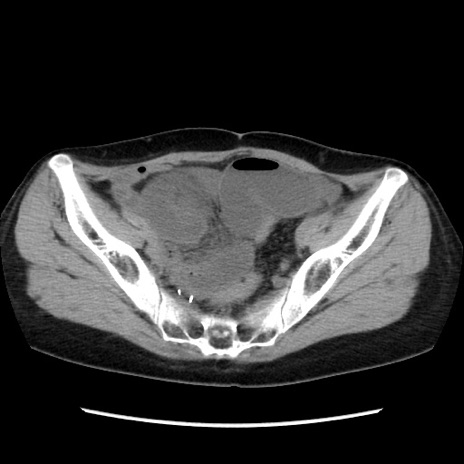

症例32(横断像)

【症例】40歳代 女性

【主訴】上腹部痛、嘔気・嘔吐

【現病歴】約9時間前頃から急に上腹部痛、嘔気、嘔吐が出現。改善しないため救急要請。

【既往歴】子宮頚癌(広汎子宮全摘術、放射線療法)、腸閉塞

【身体所見】腹部:平坦、軟、腸雑音亢進、上腹部を中心に腹部全体に圧痛あり。

【データ】WBC 8400、CRP 0.03